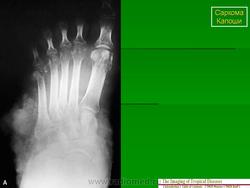

A44917_4_En_16_Fig5_HTML.jpg

Рисунок 16.5

Саркома Капоши у 35-летнего мужчины